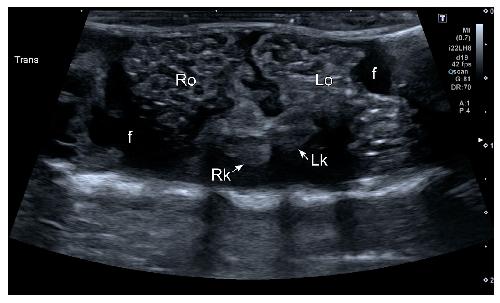

Figure 6. HR-US image of a female Kaloula pulchra obtained in the transverse plane using a ventral acoustic window. The image was taken just after oviposition. Both ovaries (right ovary: Ro; left ovary: Lo) appeared as hyperechoic structures with multiple hypoechoic foci which represent follicles. The kidneys are also visible (right kidney: Rk; left kidney: Lk). This animal had free fluid (f), which is considered normal in amphibians. The fluid around the ovaries improves its margin definition.